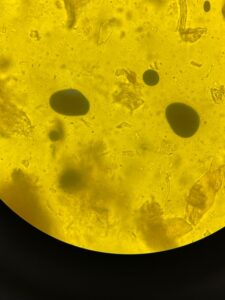

ルゴールはこんな感じ↓

黒紫色に見えるのがデンプンです。

糞便の中にデンプンが見えるということは糖質の吸収・消化障害があるかもしれません。